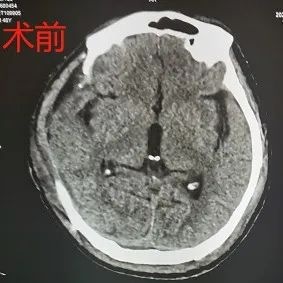

2021年8月19日,杨先生不慎从工地高处坠落,被紧急送至当地医院,入院后行头胸CT检查,提示右侧额颞顶脑挫伤伴硬膜下出血,蛛网膜下腔出血,枕骨骨折,左锁骨骨折,左肩胛骨骨折,左侧多肋骨骨折,胸椎横突骨折。因病情危重,在经过一系列抢救后,被送入了ICU病房。

手术前